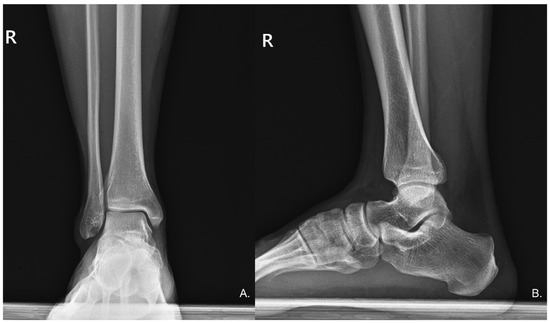

Physical examination revealed an antalgic gait during ambulation to the consultation area. Palpation elicited significant tenderness in the posterior calcaneal region, with passive dorsiflexion of the right ankle provoking substantial discomfort. A well-demarcated psoriatic plaque was observed on the right calf (Figure 1), correlating with the patient’s six-year history of psoriasis for which no active treatment was being administered. Neuromuscular assessment demonstrated decreased pin-prick sensation in the sural nerve distribution distal to the psoriatic plaque. A Tinel’s sign was positive, with percussion over the psoriatic plaque eliciting concordant paresthesias radiating distally along the anticipating pathway of the sural nerve. The remainder of the comprehensive neurological evaluation of the lower limbs yielded unremarkable findings. Standard anteroposterior and lateral radiographs of the ankle revealed no structural abnormalities (Figure 2).

Figure 2.

(A) Anteroposterior (AP) and (B) Lateral radiographs of the right ankle show no radiographic evidence of deformities or other significant bony abnormalities.